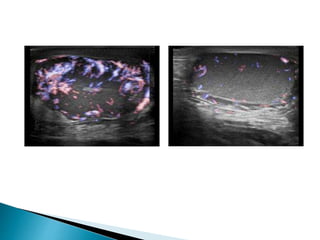

 On ultrasound the epididymis shows swelling,

 Diffuse or patchy reduction in echogenicity,

 Doppler ultrasound demonstrates

hypervascularity.

 Doppler ultrasound show increased

vascularity

 On ultrasoundthe epididymis shows swelling,  Diffuse or patchy reduction in echogenicity,  Doppler ultrasound demonstrates hypervascularity.  A heterogeneous pattern of predominant increase in echogenicity is more frequently associated with chronic epididymitis.  Often an associated hydrocele  Edematous thickening of the overlying skin  There may be coexisting orchitis